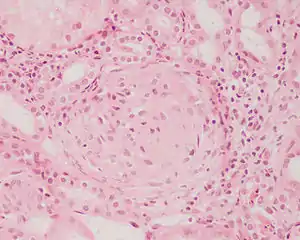

| Photomicrograph of a kidney biopsy from a person with crescentic glomerulonephritis showing prominent fibrocellular crescent formation and moderate mesangial proliferation in a glomerulus. Hematoxylin and eosin stain. | |

Rapidly progressive glomerulonephritis, also known as crescentic GN, is characterised by a rapid, progressive deterioration in kidney function. People with rapidly progressive glomerulonephritis may present with a nephritic syndrome. In management, steroid therapy is sometimes used, although the prognosis remains poor.[9] Three main subtypes are recognised:[4]: 557–558

Histopathologically, the majority of glomeruli present "crescents". Formation of crescents is initiated by passage of fibrin into the Bowman space as a result of increased permeability of glomerular basement membrane. Fibrin stimulates the proliferation of endothelial cells of Bowman capsule, and an influx of monocytes. Rapid growing and fibrosis of crescents compresses the capillary loops and decreases the Bowman space, which leads to kidney failure within weeks or months.